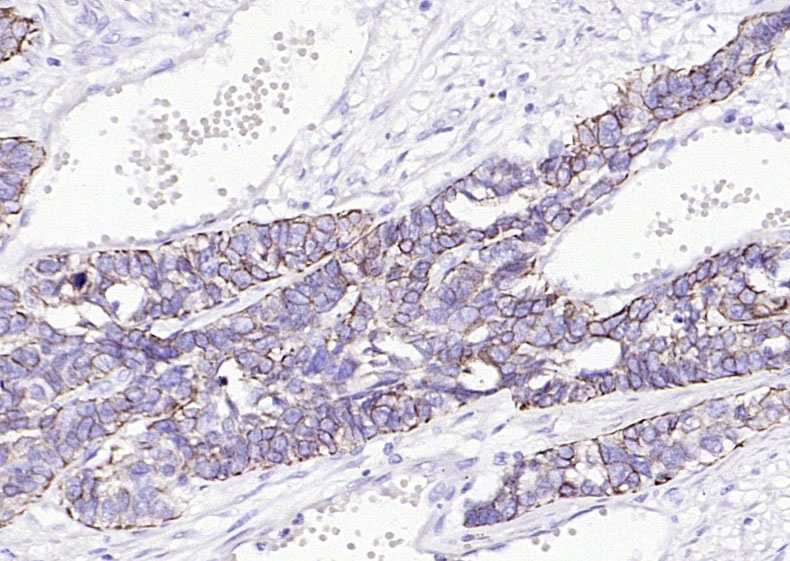

IHC-PHuman1:100-500

细胞角蛋白17单克隆抗体-bsm-33087M细胞角蛋白17单克隆抗体-bsm-33087M细胞角蛋白17单克隆抗体-bsm-33087M细胞角蛋白17单克隆抗体-bsm-33087M细胞角蛋白17单克隆抗体-bsm-33087M细胞角蛋白17单克隆抗体-bsm-33087M细胞角蛋白17单克隆抗体-bsm-33087M细胞角蛋白17单克隆抗体-bsm-33087M细胞角蛋白17单克隆抗体-bsm-33087M细胞角蛋白17单克隆抗体-bsm-33087M细胞角蛋白17单克隆抗体-bsm-33087M细胞角蛋白17单克隆抗体-bsm-33087M